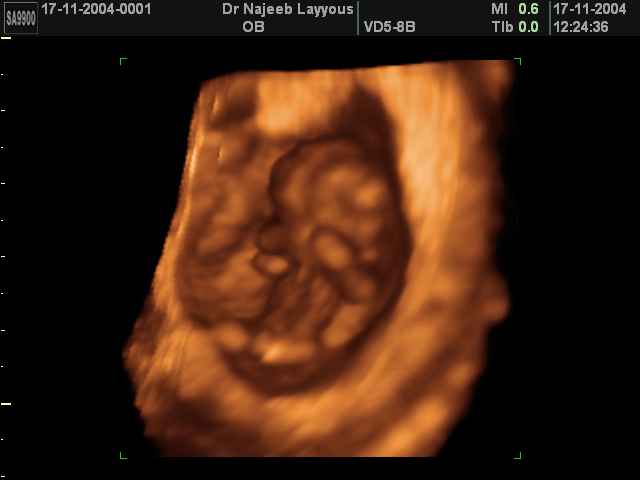

3D First Trimester Ultrasound Scan Photos